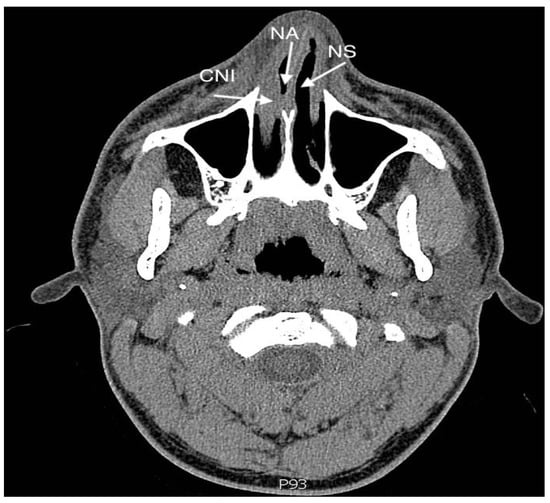

3.1.2. The Use of Nasal Splints in Septoturbinoplasty